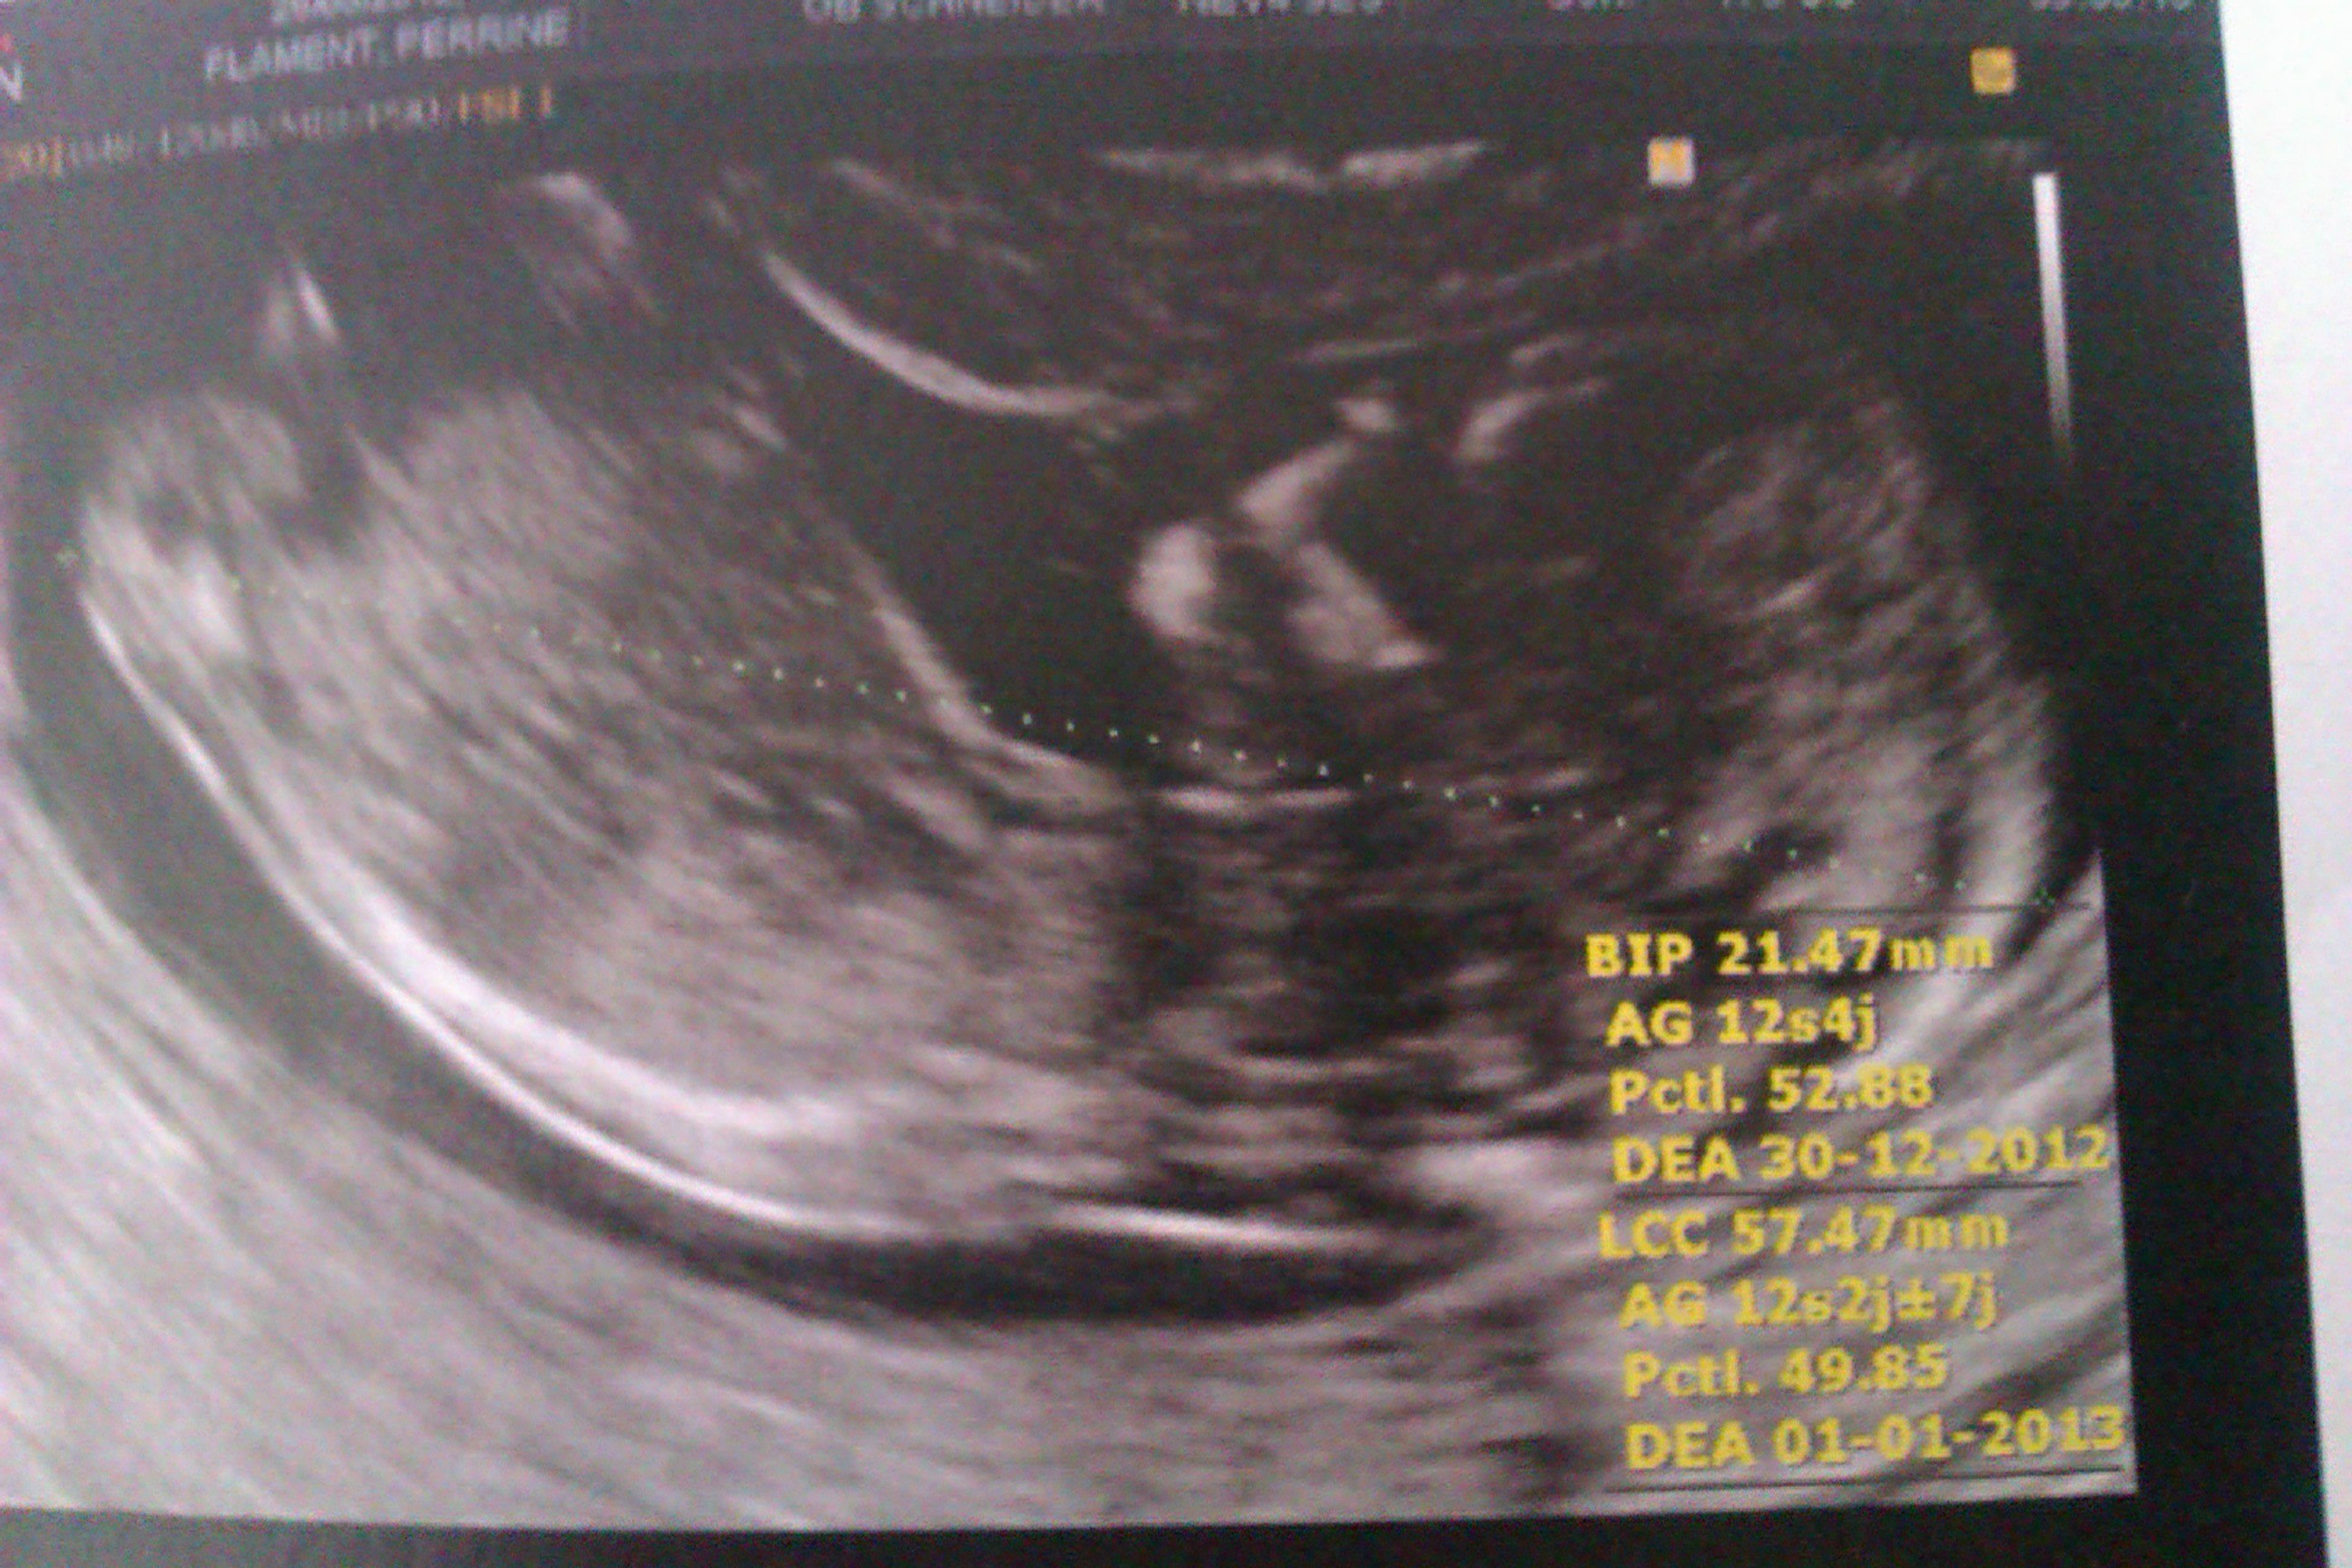

Voila les photos, la première ce sont ses fesses avec selon lui le zizi et les testicules

Félicitation perrine pour ce tit boy.